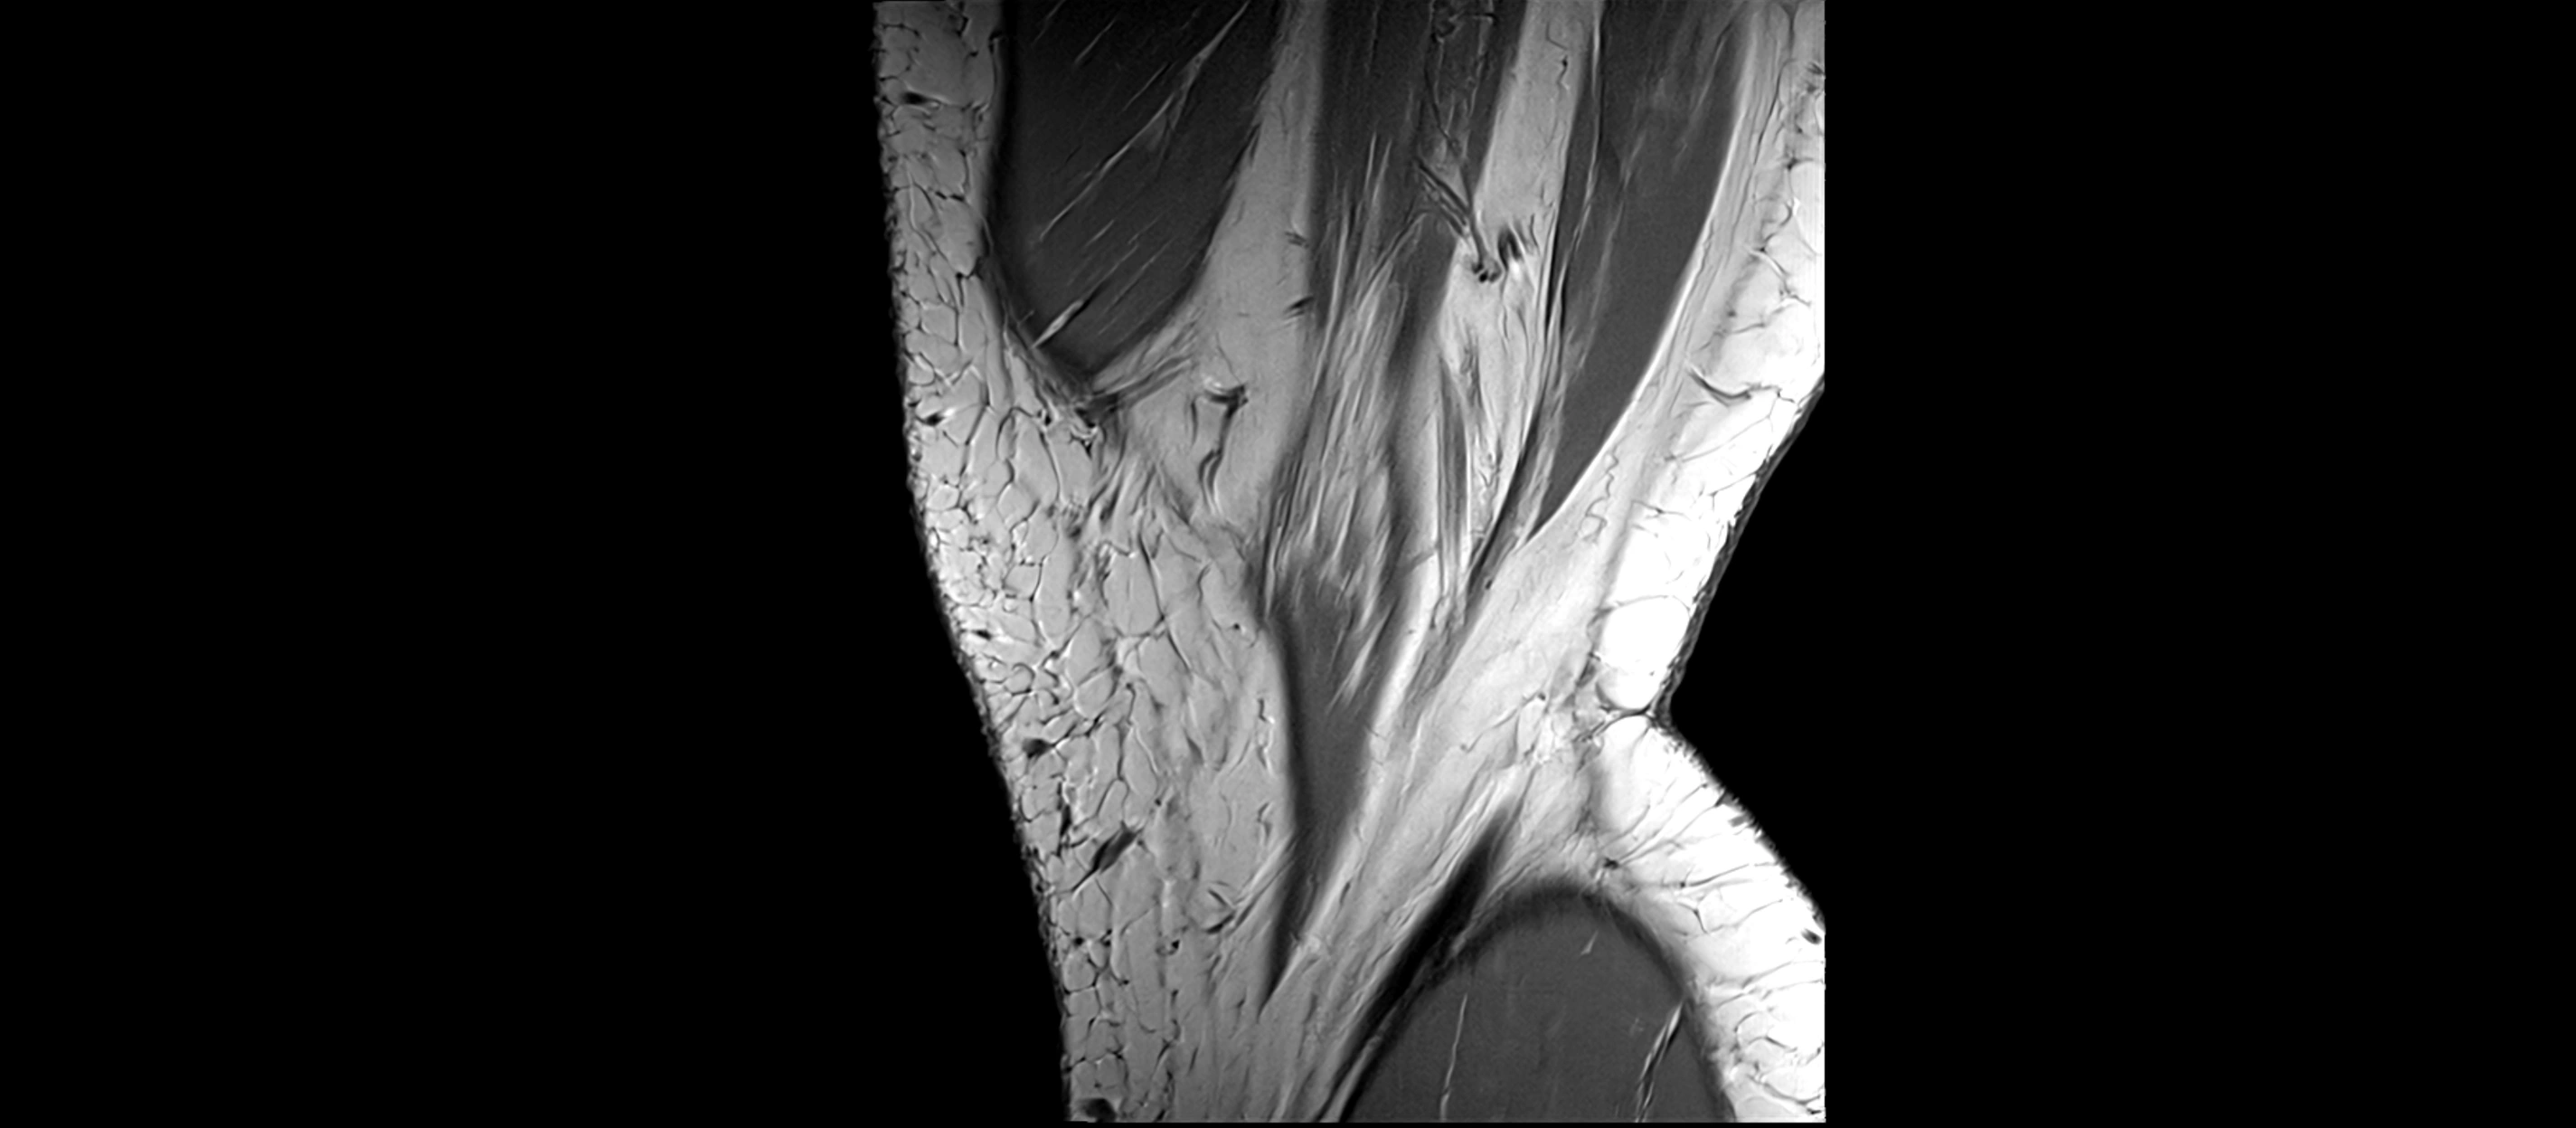

MRI Appearance

T1-weighted images:

• Normal ACL appears as a low-signal band-like structure crossing the intercondylar notch

• Surrounded by intermediate signal synovial fluid and fat planes

T2-weighted images:

• Normal ACL remains low signal

• Partial or complete tears appear as discontinuity, increased signal, or fiber laxity

MRI images

image